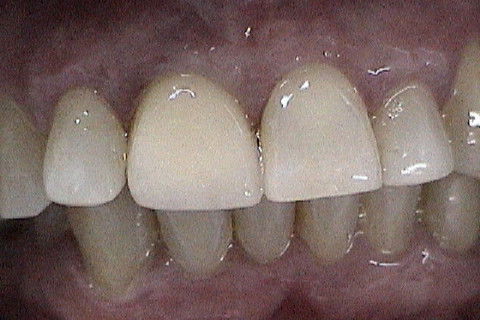

Vista vestibular da coroa metalo-ceramica

Aspecto da coroa metaloceramica no elemento 11

Paciente com fratura do elemento 11. Como havia grande perda óssea vestibular, optamos por fazer implante primeiramente a extração do dente e após 4 meses a colocação do implante. Concomitante 'a colocação do implante, enxerto óssseo + membrana para regeneração óssea foi colocado e aguardamos 6 meses para então fazermos a reabilitação com coroa metalo-ceramica parafusada.